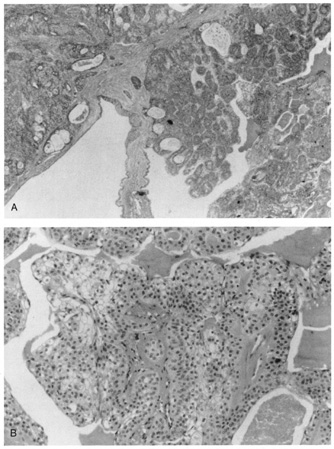

Histologic findings in normal periorbital skin are similar to other areas of the body with a keratinizing epidermis and a prominence of sebaceous glands and blood vessels (Fig. 1, A and B). Lid skin is very thin, its epidermis is composed of only a few layers of keratinocytes (squamous cells), there is an absence of the typical rete ridge (digitated) pattern, and there is a sparse dermis composed of fine fibrillar collagen fibers. Virtually every inflammatory dermatosis and cutaneous neoplasm may, at times, affect the periorbital skin and lids, but some inflammatory processes and neoplasms are commonly seen in this area, and a few are quite specific to the area.

Fig. 1. A. Photomicrograph of normal periorbital skin. B. Schematic of normal periorbital skin.